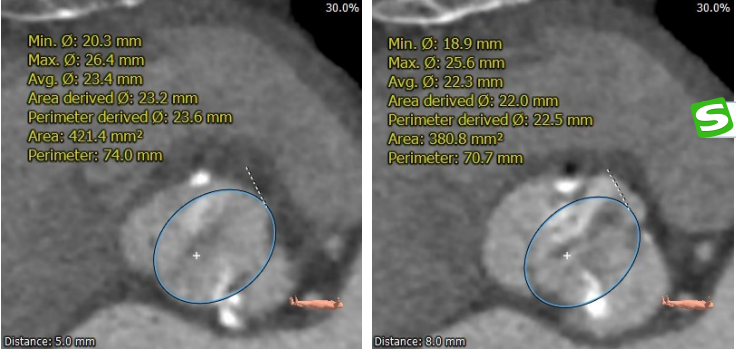

主动脉根部测量

术前陈晓敏教授带领团队对这位患者进行了详细的分析,从CT分析结果显示,患者主动脉瓣为type 0型二叶瓣,瓣环直径为24.4mm,结合患者瓣叶钙化等情况,符合美敦力Evolut PRO 29mm瓣膜选型。经讨论决定以右侧股动脉为主入路,左侧股动脉为辅入路,术中进行23mm球囊预扩张,保证系统顺利跨瓣及释放,并采用世界先进的Cusp Overlap技术植入瓣膜 ,以更精准地释放瓣膜深,减少对患者传导系统的影响。